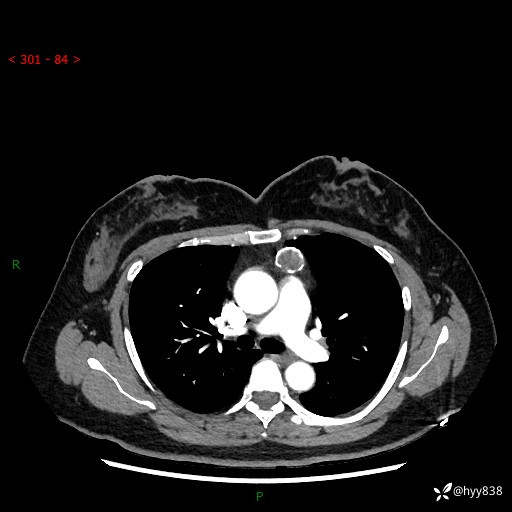

中年女性,检查发现纵隔占位3月余。圆圆的肿物,周围环绕一圈钙化---结果公布~

主诉:检查发现纵隔占位3月余。

现病史:患者于3月前体检行胸部CT检查发现纵隔占位,患者平素无明显咳嗽咳痰,无心慌、胸闷、胸痛、呼吸困难、低热、盗汗,无头痛、头晕,无腹痛、腹胀等不适。现患者欲求进一步治疗,遂来我院就诊,以“纵隔占位”收入我科。 患者自起病以来,精神可,睡眠可,饮食可,大小便正常,体重无明显改变。

胸部CT平扫+增强